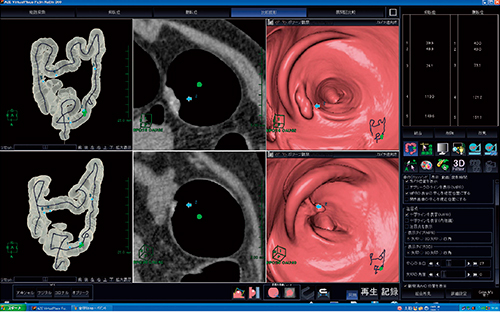

1.2体位比較読影のレイアウト

比較読影(図1)と展開図比較(図2)のレイアウトは,図で示した以外にも多彩なレイアウトが用意され,自由な変更が可能である。

図1 2体位比較読影のレイアウト:比較読影画面

観察方向,位置が同期されており,読影が容易である。

図2 2体位比較読影のレイアウト:展開図比較画面

開き画像は腸管径展開で歪みがなく,読影が容易である。